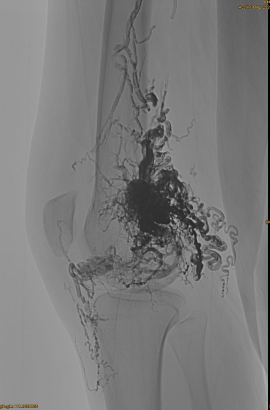

Maklumat asas pesakit: wanita, 36 tahun; AVM pelvis, pinggul, lutut, kiri OSG, pelbagai pra - embolisasi.

Produk yang digunakan: 3pcs lava-34,14pcs lava-18.

Hasil akhir:

Hampir tidak ada aliran keluar vena:

Fasa lewat, satu lagi embo diperlukan, tetapi jauh lebih baik: